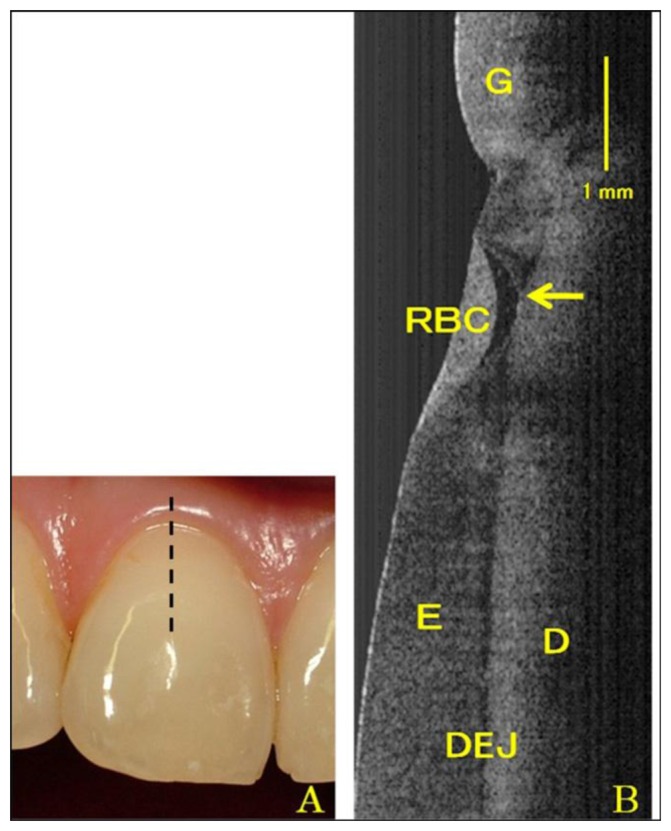

Figure 6.

Photogragh (A) and SS-OCT image (B) of Class V restoration in the central incisor. Arrow shows microleakage formation beneath resin material (G: gingival; RBC: resin based composite; E: enamel; D: dentin; DEJ: dental enamel junction) (reprinted from reference [54]).